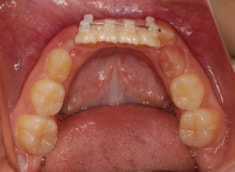

治療開始から11ヶ月